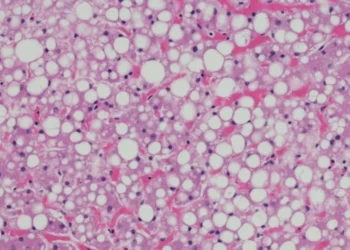

Adultos com gordura no fígado têm 30% mais risco de diabetes tipo 2

Estudo realizado por pesquisadores da Universidade Federal de Minas Gerais (UFMG), em parceria com cientistas da Universidade de São Paulo (USP) e da Universidade Federal do Rio Grande do Sul...